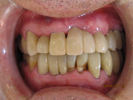

50代女性

![]() |

治療前 |

||

治療中。仮歯。 左上の奥にインプラント埋入。 噛みあわせ治療を行いました |

治療後 全体の歯で食事がおいしくできるようになったと喜んでおられました。 |